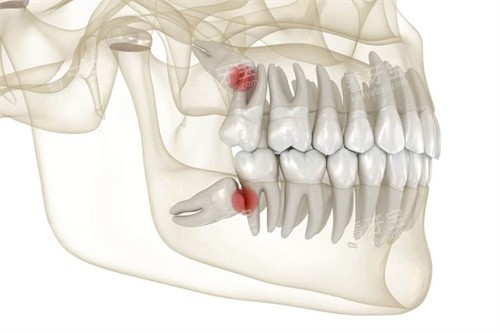

我先简单说了下智齿的情况。她没急着下结论,而是先让我躺下,做了一次齐全的口腔检查。用的是一次性的口镜和探针,这个细节让人安心。她一边看,一边会同步告诉我她看到的情况:“你这颗智齿长得有点歪,和前面的牙齿形成了一个小凹槽,平时容易藏东西,自己可能不好清洁……这边有颗大牙,咬合面看到有个非常小的黑点,我轻轻探一下,你感觉酸吗?不酸?那可能只是色素沉着,但我们可以定期观察……”

整个过程大约持续了十几分钟。她不仅看了我主诉的智齿,还仔细检查了每一颗牙的牙面、牙龈状况,甚至简单看了下我的咬合关系。结束后,她让我坐起来,走到一旁的电脑前调出刚才拍摄的影像(一种小范围的X光片),指着屏幕上的影子,开始解释。

2. 沟通:方案与选择权

关于智齿,她的分析很直接:“从片子上看,牙根形态还算规整,但完全埋在牙龈下面,顶到了前面的牙。现在虽然没有急性发炎,但长期来看,清洁不到位可能引发前面那颗好牙的蛀牙,或者导致牙龈反复发炎。拔除是一个可以考虑的选择。”

她并没有强调“必须立刻拔”,而是列出了几种可能性:如果暂时不想处理,需要特别注意用牙线清洁那个位置;如果选择拔除,大概的流程、时间以及后续需要注意些什么,她都一一说明。尤其提到了拔牙过程中可能会有的一些感觉,以及如何配合能让自己更轻松。